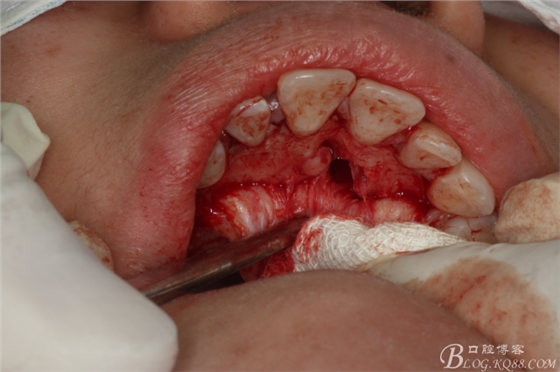

圖13.去骨、暴露11腭側(cè)部分多生牙

圖14.逐漸暴露出的多生牙